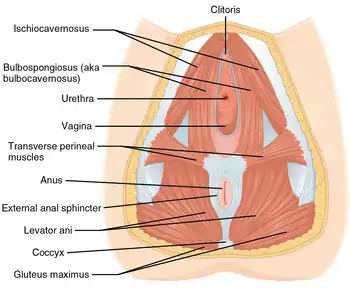

Muscles of the male perineum Muscles of the female perineum

Muscles of the female perineum The posterior aspect of the rectum and anus exposed by removing the lower part of the sacrum and the coccyx